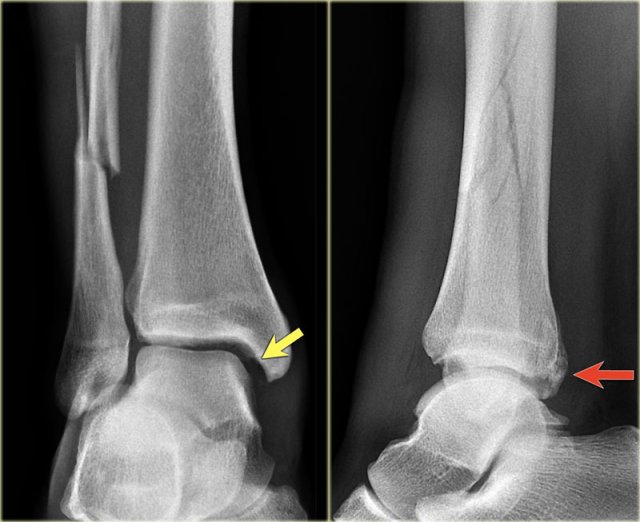

Weber B fracture Weber B fracture

The radiographs show a typical Weber B fracture.

First study the images and then continue reading.

Do you see what stage this is?

This is a Weber B stage 4 injury.

Notice that all 4 stages are visible:

1. Rupture of the anterior syndesmosis - seen as widening of the space between the distal tibia and fibula (lateral clear space).

2. Oblique fibula fracture at the level of the syndesmosis - i.e. Weber B fracture.

3. Tertius fracture - seen on AP view (red arrow) and on lateral view (yellow arrow).

4. Rupture of the medial collateral ligaments - seen as widening of the space between the medial malleolus and the talus (medial clear space)